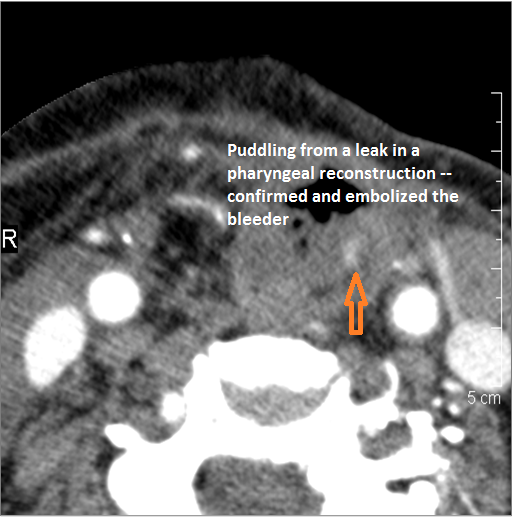

Vascular Findings

There is evidence of active extravasation from an arterial or venous source.